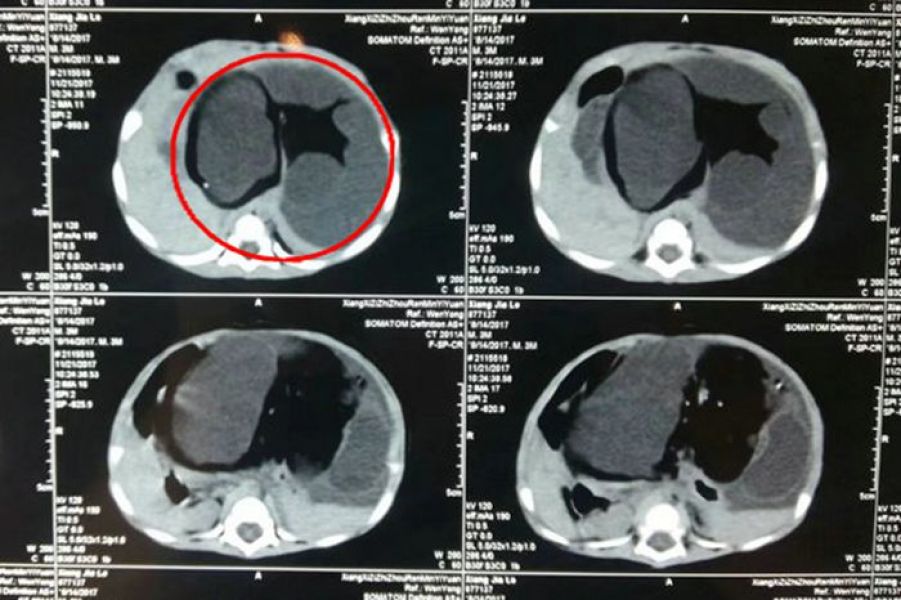

11月26日上午10时,在州人民医院普外五科正在进行一场特殊病例的术前讨论。该患儿年龄仅3个月,体重6公斤,因发现患儿腹胀、呕吐1个多月入院。医生给患儿体格检查发现其外观瘦弱,腹部明显隆起如球状,可扪及巨大肿物,质地坚硬,表面凹凸不平。腹部CT检查提示巨大腹膜后肿瘤,肝脾向两侧移位,胃变形移位,肠管均位于下腹及盆腔,腹部大血管受压,考虑畸胎瘤可能。肿瘤标志物检查甲胎蛋白等多项阳性。讨论会上,大家认为,患儿年龄小,肿瘤大,肿瘤根部位置深在腹膜后,周围有大量重要血管包绕,手术难度较大,这对于10月21日才成立的普外五科(主攻小儿普外科及疝与腹壁外科专业)是一种挑战。

普外五科决定迎难而上,科室医务人员既往有多次成功切除小儿腹腔肿瘤的经验,但对于年龄仅3个月,肿瘤直径达到13.9厘米的患儿病例还是第一次遇到。经过与家属积极沟通,讲明手术必要性及其危险性,患儿家属表示理解同意手术。麻醉评估、术前备血、水电解质平衡紊乱的纠正等术前准备随即展开。

图中红色标记框内为肿瘤